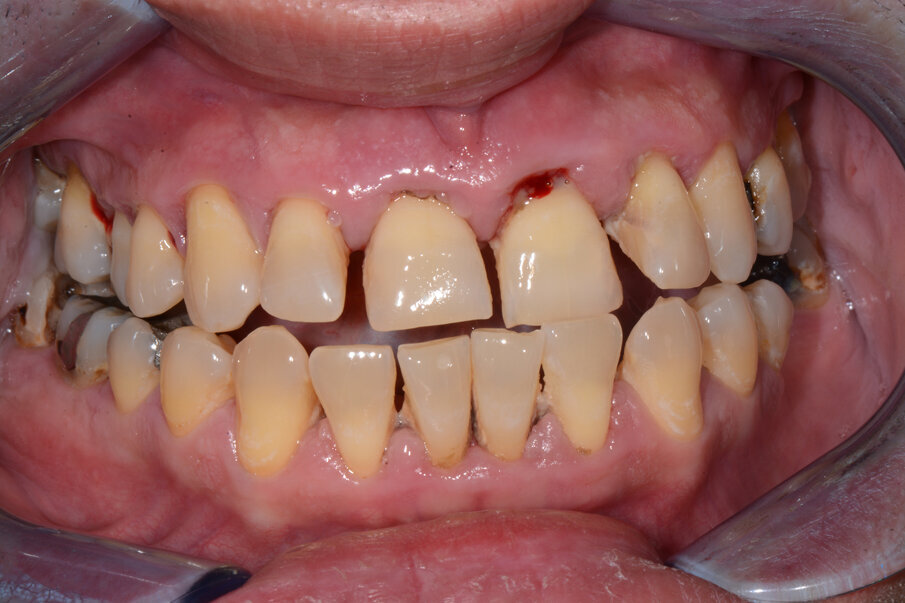

Pacijent starosti 29 godina, s agresivnom formom parodontitisa. Pacijent je u trajanju od 2 godine lečen nehirurškom, a zatim i hirurškom terapijom oboljenja parodoncijuma uz primenu preparata GelCide. Nakon 2 godine, pacijent je protetski rehabilitovan fiksnim protetskim radom.